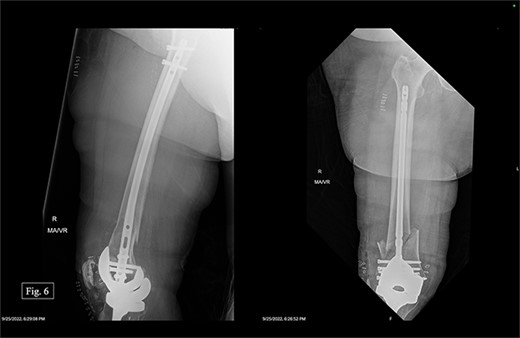

The patient was positioned supine with a radiolucent triangle under the operative knee. A trans-patellar approach was made for our T2 alpha retrograde nail measuring 10 × 330 mm. We confirmed the appropriate purchase with fluoroscopy and placed the distal interlocking screws through the implant. The distal articular block was noted to be slightly valgus; however, it appeared appropriate when assessing her mechanical and clinical alignment. The patient experienced 100 mL of intraoperative blood loss, awoke without incident, and was admitted to the ICU for monitoring and management. Postoperative APand lateral X-rays were taken (Fig. 6).